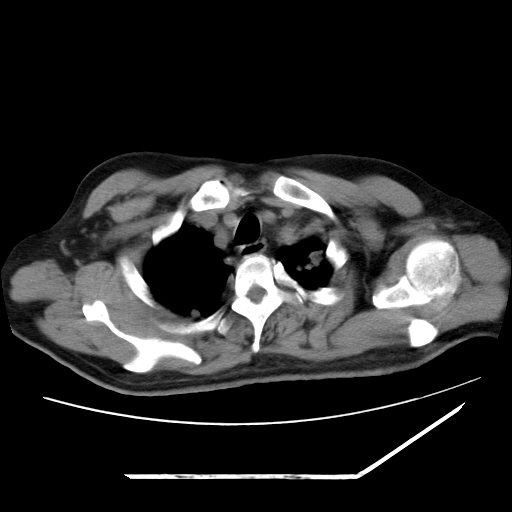

男,57,畏寒,发热

两肺野多发大小不一高密度灶,纵膈内见肿大淋巴结,要考虑转移瘤可能。双侧胸腔少量积液。

双肺多发结节样病灶,部分内见透光区,纵隔内见淋巴结肿大。结核临床如有畏寒,高热,白细胞增高首先考虑迁徙性肺脓肿(多是金黄色葡萄球菌感染)。

注意除外转移瘤。